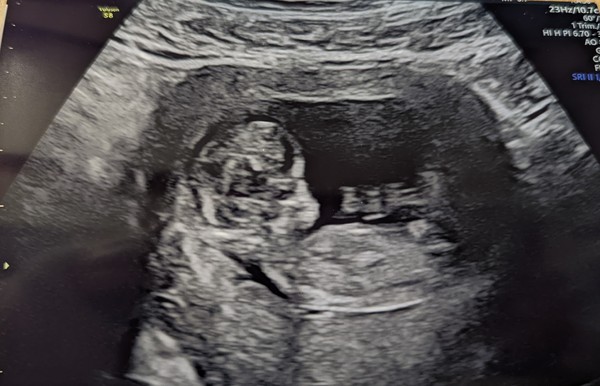

All was good, bubs is measuring 11+6 saw and heard the heartbeat. Bubs very wriggly and sonographer said all looks well but also have my nhs scan in 2 wks

Sooo reassuring xx

Forgot to attach a pic x

@strawberrysummer19 what a fabulously clear scan picture! Congratulations 🙂 Such a relief isn't it xx